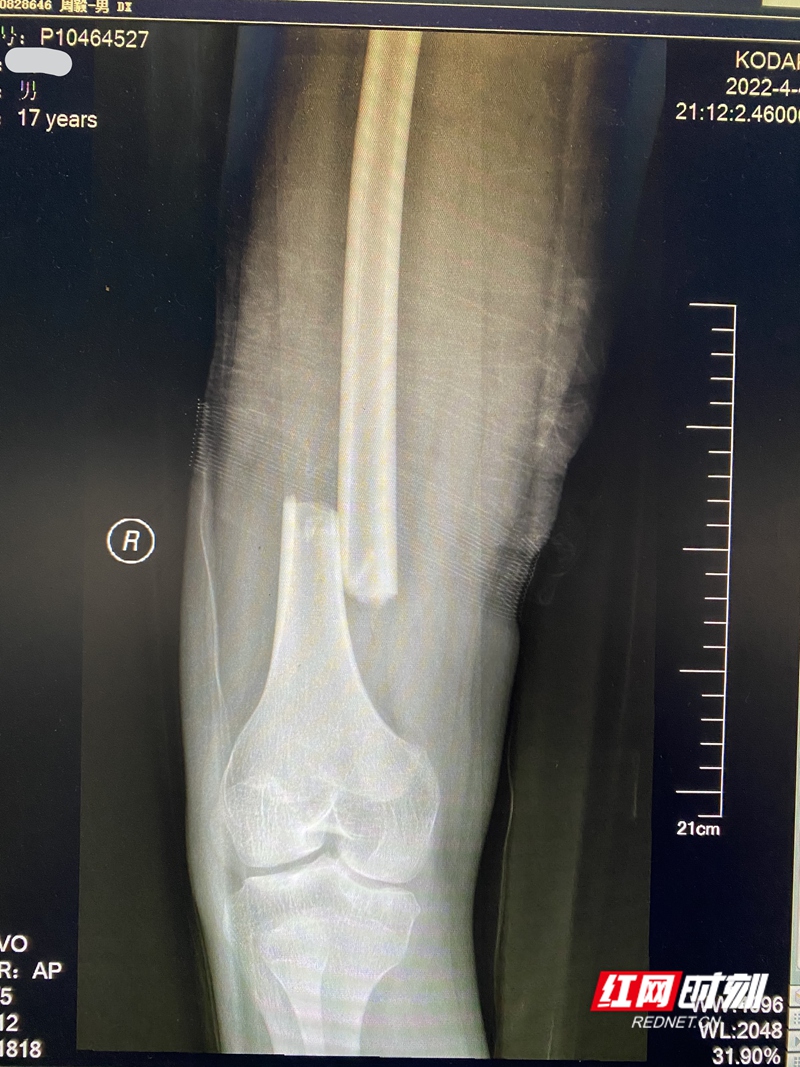

股骨骨折是创伤骨科的常见病,怀化市第一人民医院治疗股骨骨折的手术也已经做得炉火纯青了,但一次意外摔伤后导致左股骨骨折的小周(化名)让创伤骨科的医疗团队顿感棘手。

今年17岁的小周患有血友病,这是一种因为患者体内某种凝血因子缺乏,使得患者凝血功能异常,即使一个小小的伤口,也会因为血液不凝固导致出血不止而危及生命的病。由于大腿肌肉发达,股骨在大腿肌肉深处,常规的股骨手术出血都比较多,而小周的病情更不允许骨科医师按常规的手术来进行股骨内固定治疗。

医院对患者的治疗高度重视,在副院长胡文祥的组织下,血液科、创伤骨科、麻醉科、重症医学科等相关科室多次大会诊,咨询了多家上级医院的意见,为该患者定下了治疗方案:在补充足量的凝血因子后,牵引复位、微创外固定架固定复位后的股骨。

一切准备就绪后,医疗团队在4月18日为患者进行手术。骨科主任李健亲自操刀,术中仅仅应用了一个长约5cm的手术切口辅助复位,再外固定架牢靠的外固定,手术过程顺利,术后按足量输凝血因子,患者伤口出血量得到控制,如期安全拆线出院。